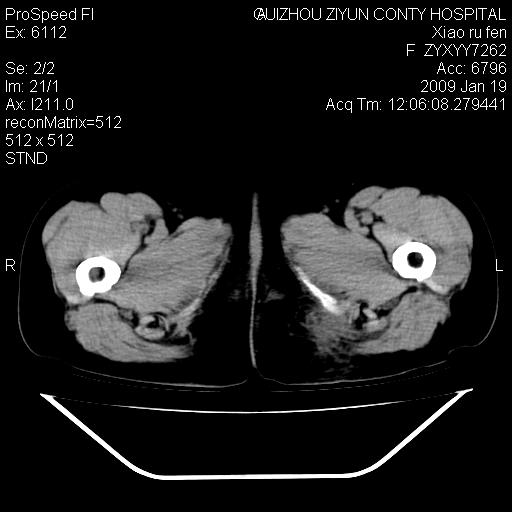

以下是引用随光逐影在2009-1-19 16:15:00的发言:[br]左侧臀部类似软组织密度肿块,性质待定(不排除肿瘤可能);建议行进一步检查。

以下是引用zbp537在2009-1-19 14:25:00的发言:[br]考虑两个诊断:1、皮脂腺囊肿伴感染。2、脓肿。[br]诊断依据:[br]1、肿块为低密度,边界较清,和皮肤相连,周围结构清晰,未见受累及。[br]2、诊断脓肿是因为其内密度不均匀,当然要结合病史,因为脓肿临床上肯定表现为红肿热痛,也希望楼主把病史提供全面些,这些便于讨论。

以下是引用zbp537在2009-1-19 14:25:00的发言:[br]考虑两个诊断:1、皮脂腺囊肿。2、脓肿。[br]诊断依据:[br]1、肿块为低密度,边界较清,和皮肤相连,周围结构清晰,未见受累及。[br]2、诊断脓肿是因为其内密度不均匀,当然要结合病史,因为脓肿临床上肯定表现为红肿热痛,也希望楼主把病史提供全面些,这些便于讨论。